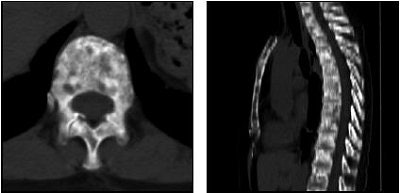

| A 63-year-old woman with osteoblastic bone metastases. Axial CT image (top left), 3D maximum-intensity-projection CT image (top right), sagittal SPECT image (bottom left), and sagittal FDG-PET image (bottom right) show osteoblastic deposits in vertebral bodies have increase in uptake of 99mTc hydroxymethylene diphosphonate (arrows), but not in uptake of FDG-PET. Hypermetabolic lesion in mediastinum (arrowhead) was confirmed to be lymph node recurrence. |

PET scans (Advance NXi, GE Healthcare, Chalfont St. Giles, U.K.) were started one hour after administration of 220-240 MBq of FDG. The authors pointed out that this FDG dose is lower than the norm, but more suitable for smaller Japanese patients. Finally, patients underwent CT and MRI scans to categorize metastases as osteolytic or osteoblastic.

According to the results, SPECT's sensitivity for diagnosing bone metastases was 85%, while the specificity was 99%. For FDG-PET, the sensitivity was 17% and the specificity was 100%. For metastasis classification, SPECT detected 92% of the 143 osteoblastic lesions and 35% of the 20 osteolytic sites. In comparison, FDG-PET found 6% of osteoblastic metastases and 90% of osteolytic ones.

SPECT is more accurate for differentiating benign and malignant lesions, the group concluded. However, FDG-PET is superior to SPECT for detecting osteolytic breast cancer metastases. They attributed this to technical differences in the two modalities -- SPECT is better for assessing bone destruction by tumor cells, while PET detects metabolic activity of tumor cells. Ultimately, they recommended that bone SPECT become routine in breast cancer tracking because of its high sensitivity.